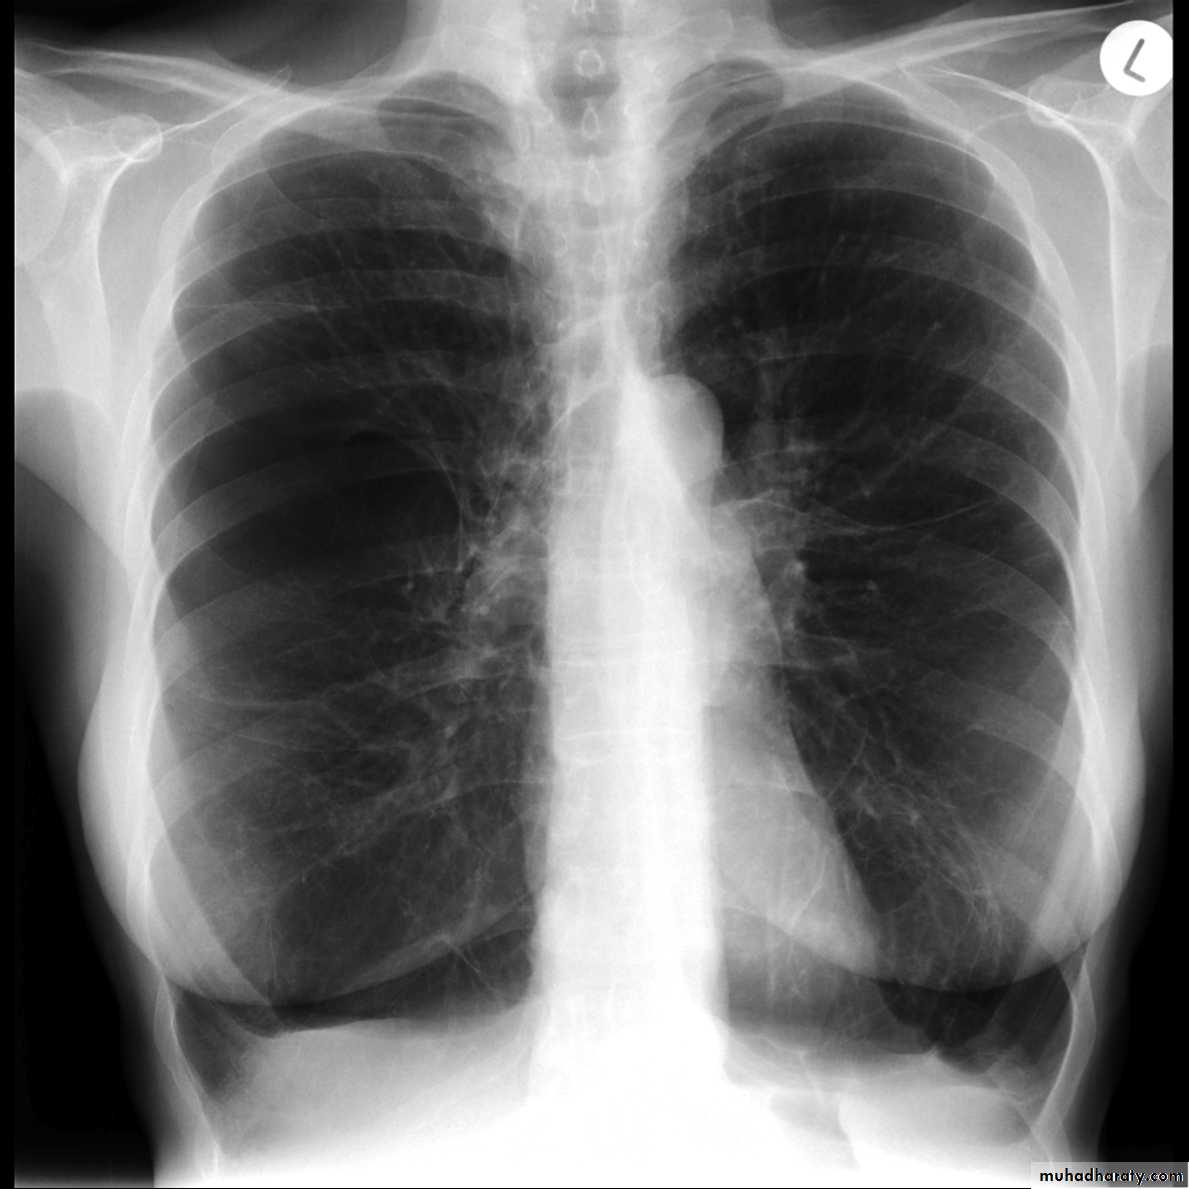

Dextro cardiaCXR of adult female , PA view shows:Cardiac shadow is seen on the right sideDiagnosis= dextrocardia